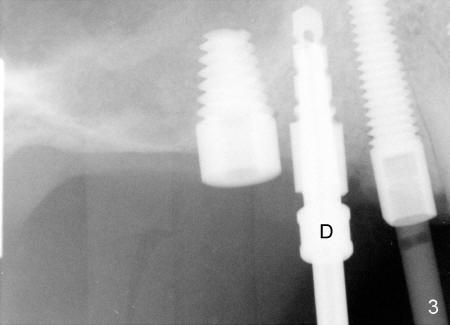

In fact, healing screws had been removed (Fig.1). There is space inside the well of the implant #5 and less obvious in that of #3 (because its wall is thicker). When implants tilt, the opening of the wells is visible (Fig.2-4).

A post guide (Fig.2: P) was inserted to the well of #5 implant as a guide for #4 pilot drill and continually for a drill with larger diameter (Fig. 3 D). Implant placement was a breeze (Fig.4). Two months later, three of the straight abutments (0 degree) were also parallel to each other.